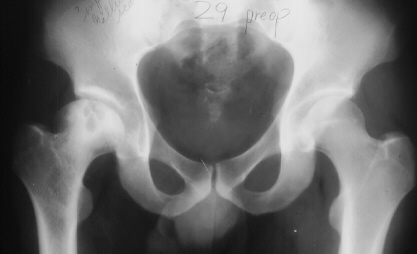

At 28 years of age, he had been having increasing pain in his right hip. He had a limp when he was tired. Positive Trendelenburg's sign was observed on the right. Internal rotation was limited to 25 degrees. All other motions were normal. X-ray showed cystic change. At the 29 years of age, he underwent bone graft of the right femoral head for degenerative cyst. At 35 years of age, only internal rotation was limited to 20 degrees. He still had pain in his hip that relates primarily to weather or to excessive walking. Only internal rotation was limited to 20 degrees. He had hip pain at the extremes of flexion and internal rotation. X-ray showed the progression of the cystic change. CT which was performed because of the question of loose bodies in the hip did not seem likely that the densities were actually in the hip joint. The antero-medial location of the cysts facing the anterior margin of the acetabulum was well depicted in CT.

28 yrs, 29 yrs, 30 yrs, 35 yrs .